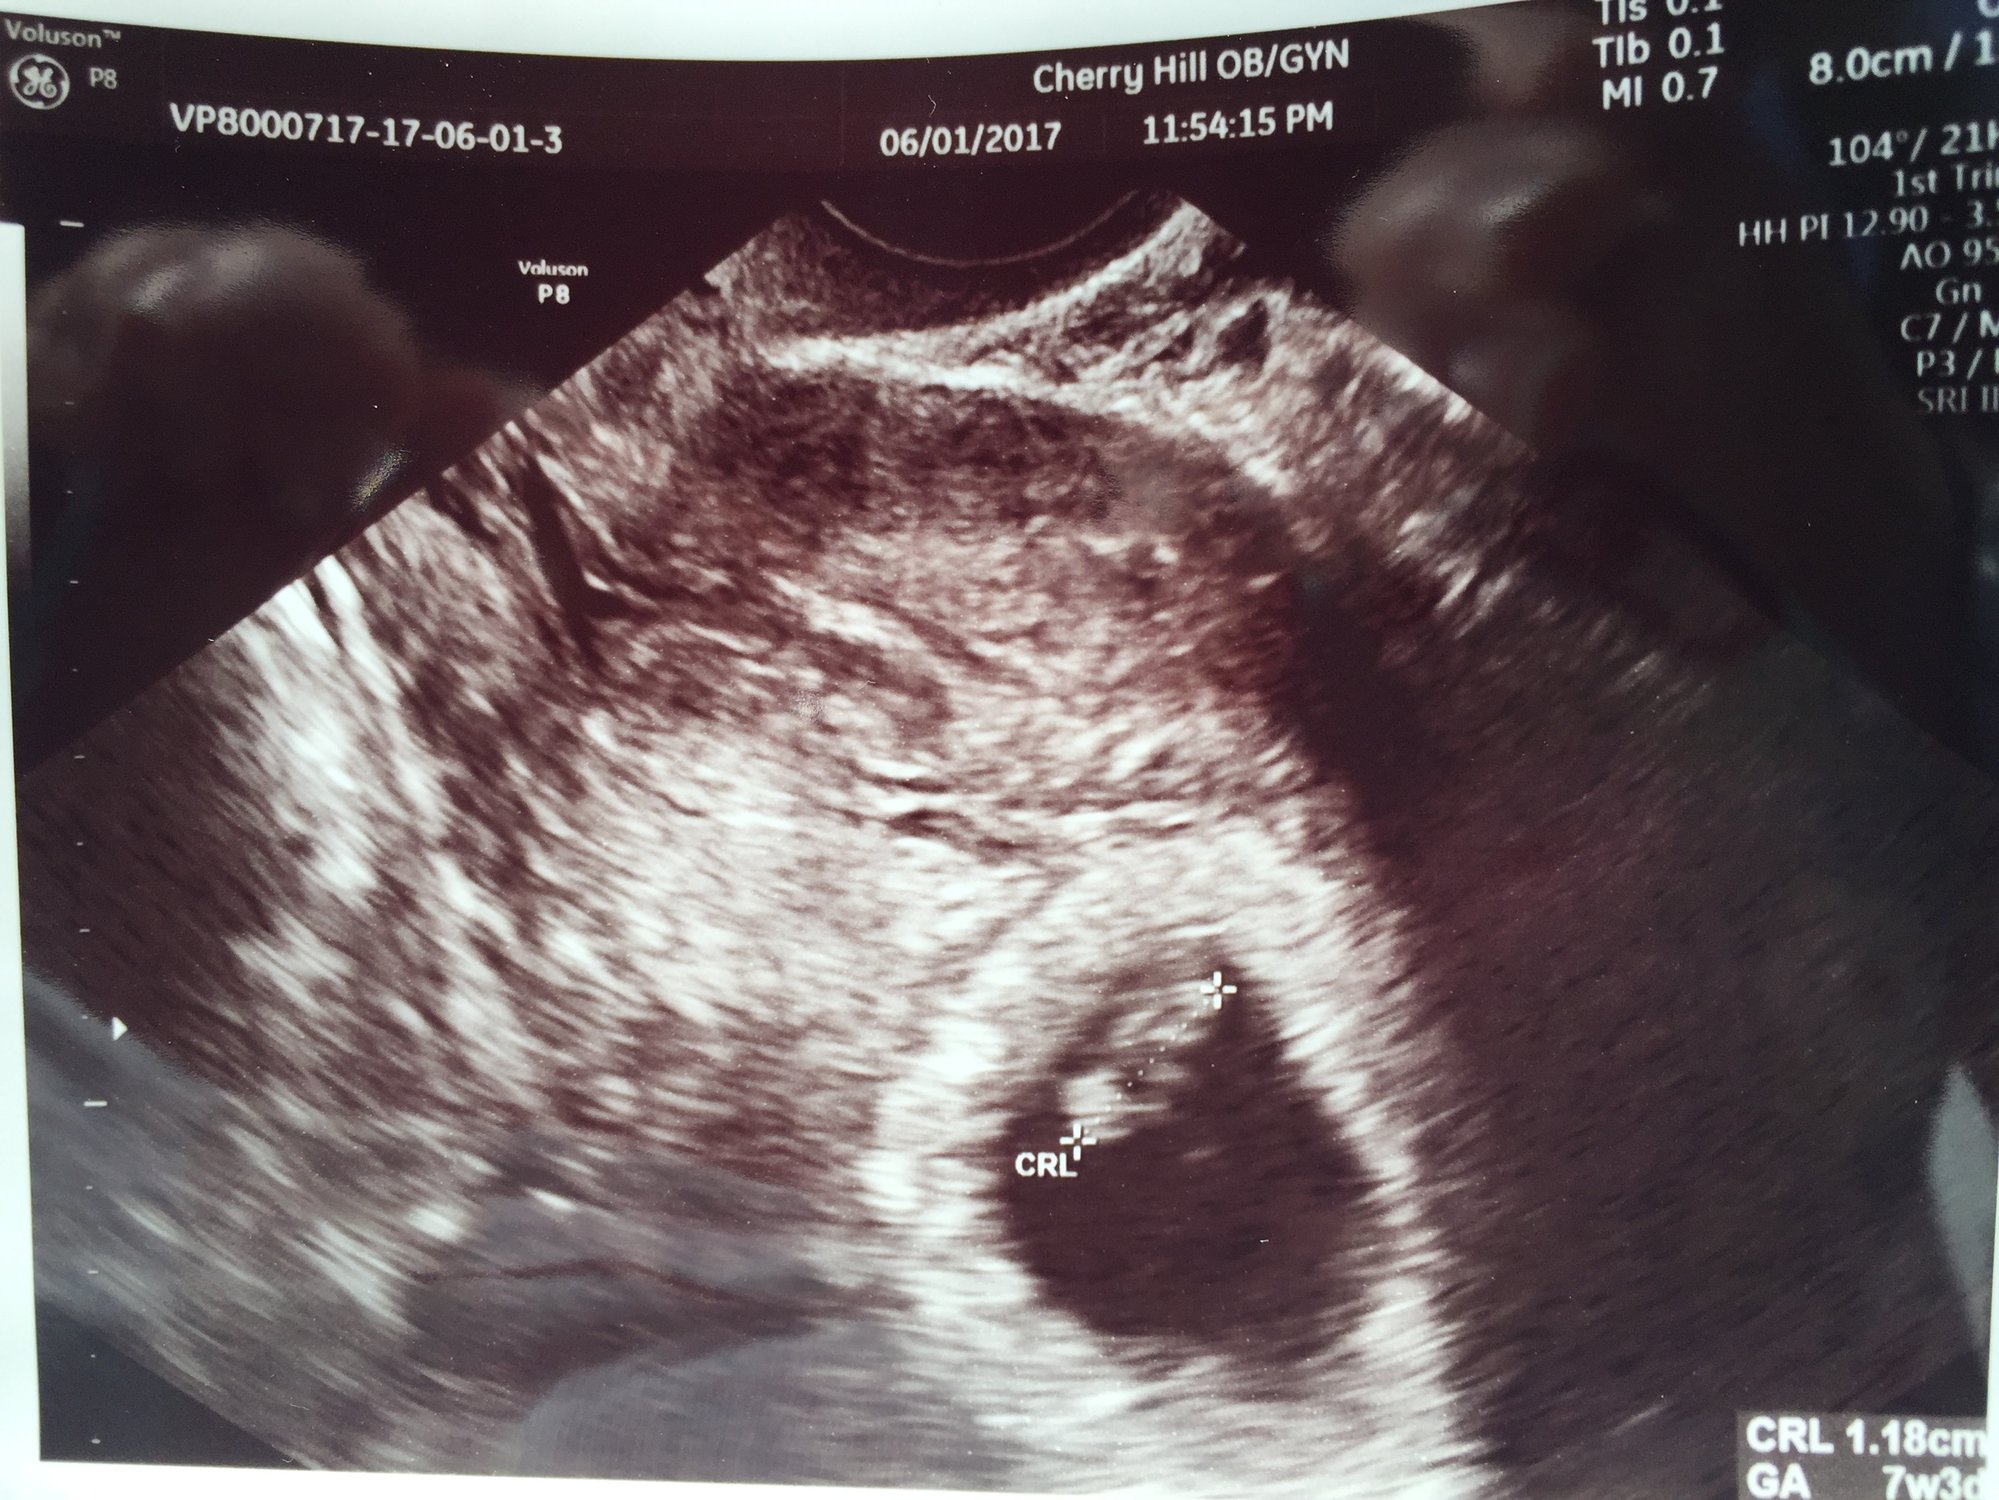

I had my first appointment yesterday!!! We saw the heart beat!!! It was 153 beats per minute and the baby measured 1.25cm. I am 7 weeks 4 days. Such a relief to see our little one